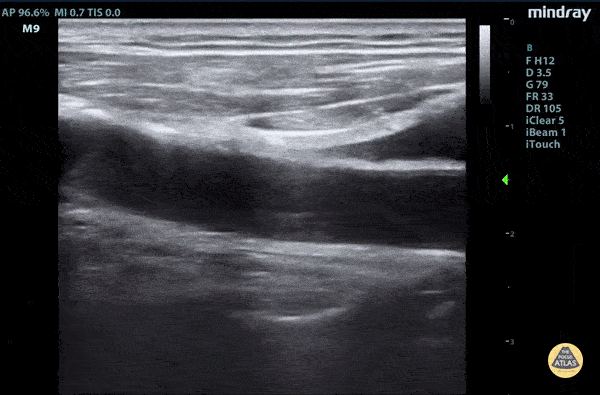

Aorta - Aortic dissection flap tamponade

Elderly fellow who had a headache while bike riding, with some leg weakness. No chest or back pain. Stable for hours then came to hospital, suddenly hypotension and drowsy in ER POCUS RUSH Exam performed lead to rapid diagnosis of Aortic Dissection with tamponade. A dissection flap can clearly be visualized. Claire Heslop - Pediatric Emergency Medicine - University of Toronto Hospital for Sick Children